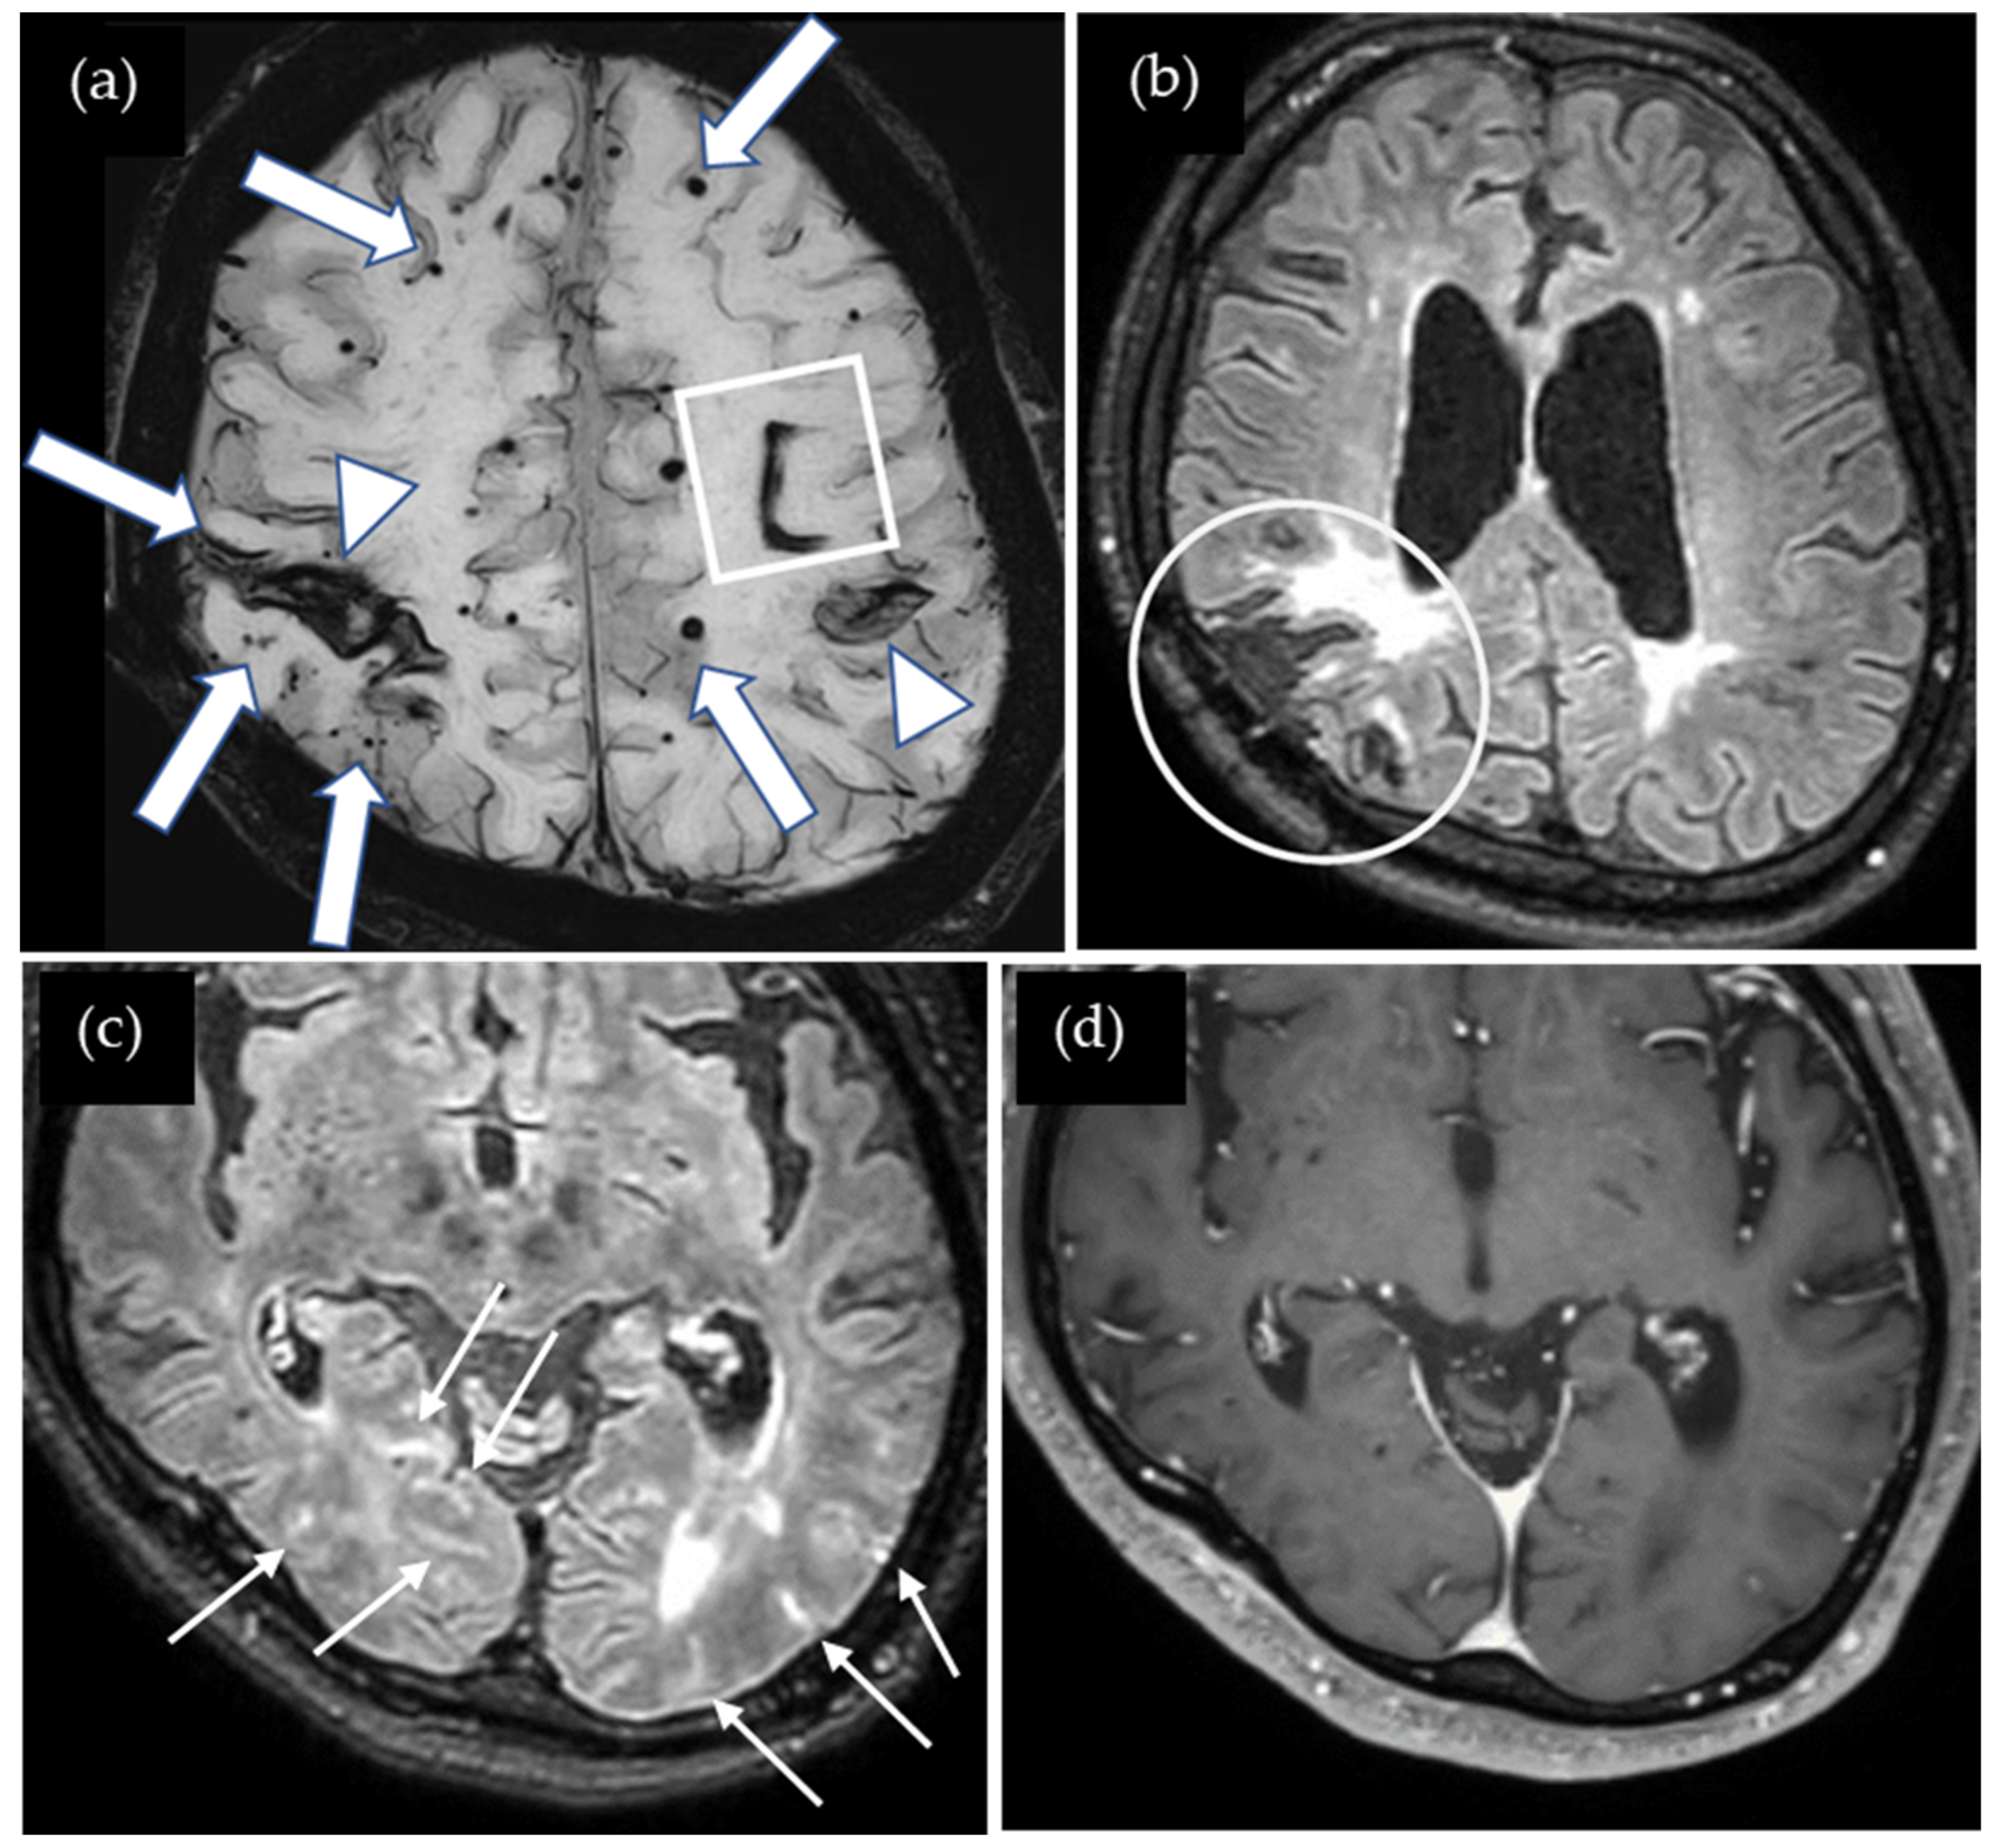

A 56-year-old man presented with sensory and motor disturbances in his left hand, which subsequently improved without specific treatment. At the age of four, he suffered a traumatic brain injury in a car accident that required cranial surgery at the right parietal region. Cadaveric dura mater use was not confirmed. He had no history of hypertension or familial CAA. CT showed lobar ICH in the right cerebral hemisphere, and SWI showed multiple lobar CMBs and cSS in both cerebral hemispheres (Figure 4). The CAA-SVD score was 6 based on the previous literature [5], consisting of two points for lobar CMBs, two points for cSS, one point for CSO-PVSs, and one point for WMH. Notably, cSS was also observed in the right postcentral gyrus, which may be associated with TFNEs. Contrast-enhanced 3D FLAIR showed enhancement in the sulci of the bilateral occipital lobes while enhancement was not detected on the contrast-enhanced 3D GRE T1-weighted image. Neither CSF examination nor amyloid PET was performed. Thus, this case was considered a possible iCAA based on the criteria [1].

Figure 4.

(a) SWI shows lobar hemorrhages (square) in both cerebral hemispheres, multiple lobar CMBs (arrows), and cortical superficial siderosis (cSS) (arrow heads). cSS in the right postcentral gyrus may be associated with TFNEs; (b) non-contrast 3D FLAIR shows postoperative changes in the right parietal lobe (circle); (c) contrast-enhanced 3D FLAIR shows sulcal enhancement in the bilateral occipital lobes (small arrows) while enhancement was not detected on (d) the contrast-enhanced 3D GRE T1-weighted image.